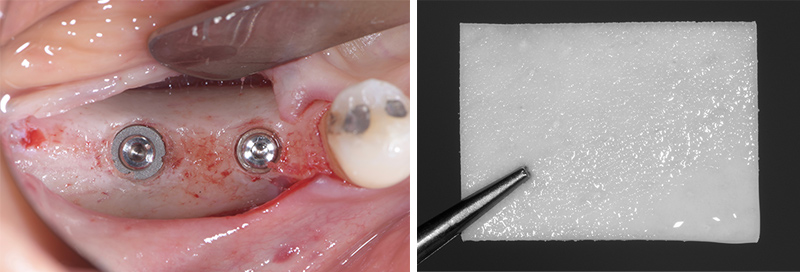

Fig. 10 : implants en place, membrane Mucoderm (Botiss).

Fig. 11 : membrane en place et sutures.